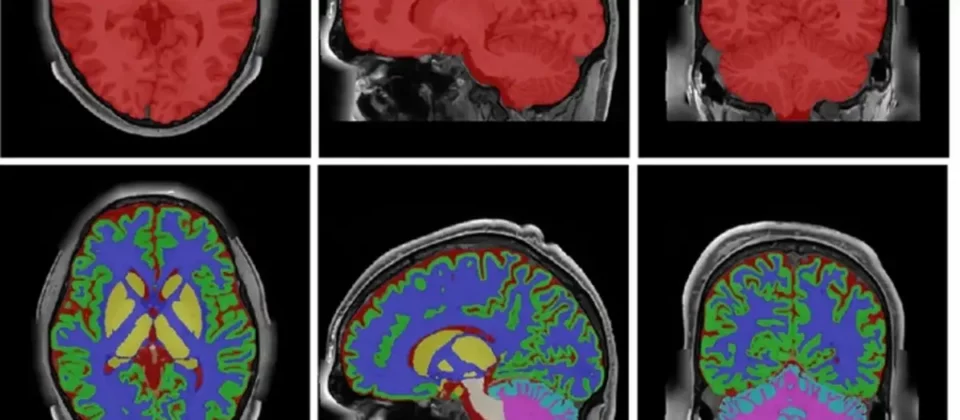

Basado en imágenes de resonancia magnética (MRI) multimodales de ultra-alta resolución, el nuevo mapa supera ampliamente el nivel de detalle de otros atlas existentes basados en imágenes de resonancia magnética.

“En su nivel más detallado, el atlas incluye hasta 350 regiones anatómicas obtenidas mediante la integración de siete protocolos de segmentación diferentes, combinando herramientas de análisis neuroanatómico, algoritmos de inteligencia artificial y correcciones manuales de expertos”, explica Sergio Morell, investigador del grupo MIA-LAB de ITACA y coautor del estudio, citado por un comunicado de la Universidad Politécnica de Valencia (UPV).

“Hasta ahora, la mayoría de los atlas basados en MRI tenían una resolución aproximada de 1 mm³. El nuevo atlas desarrollado alcanza una resolución de 0,125 mm³, lo que permite observar estructuras cerebrales mucho más pequeñas y complejas”, compara Morell.

“HoliAtlas ofrece una representación completa y multinivel del cerebro, desde estructuras globales hasta subestructuras muy específicas, de forma holística”, explica Manjón, responsable del grupo MIA-LAB de ITACA-UPV, en la web de la UPV.

Además, “su resolución y su integración multimodal facilitan la identificación de estructuras profundas y permiten desarrollar métodos de segmentación automática más precisos, mejorar el análisis morfológico y detectar cambios anatómicos muy sutiles”.